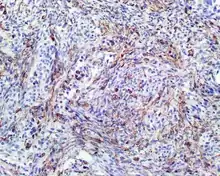

| A high power of a hematoxylin and eosin stained slide showing respiratory epithelial inclusions within a spindled cell neoplasm showing characteristics of a biphenotypic sinonasal sarcoma. | |

- Infiltrative, highly cellular spindled cell neoplasm that is poorly circumscribed and unencapsulated. Bone destruction or invasion is common. The cells show medium to long fascicles (nerve fibers,) with a herringbone pattern. The cells are remarkably uniform with elongated nuclei. There are delicate strands of intercellular collagen without ropy or dense deposition. There is a very characteristic concurrent surface-type respiratory epithelial proliferation from the surface or in small cystic spaces around the cancer cells, often forming glands. The background may have a rich vascularity (vein-ness) and usually has a small number of scattered lymphocytes. Extra growths or mitoses are rare, while necrosis, ulceration, and hemorrhage are usually absent.